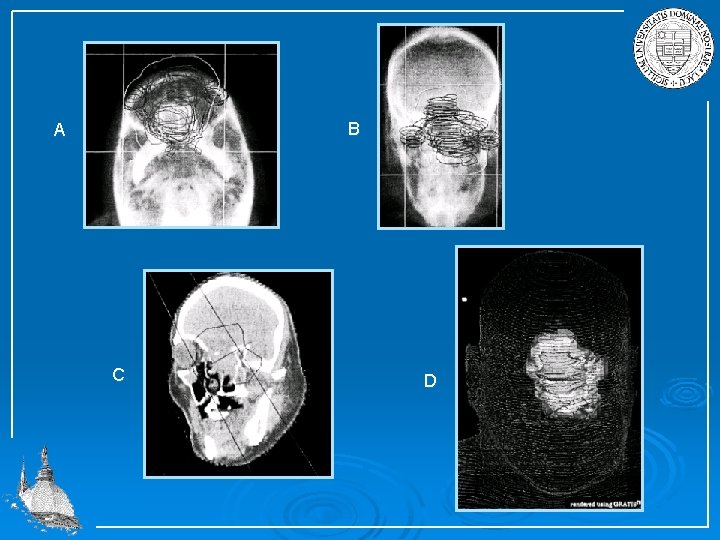

Treatment plan needs to be carefully designed, should rely on careful localization of tumor with modern imaging techniques (CT, MRI). Dose and dose losses should be simulated (three dimensional simulation).

B A C D